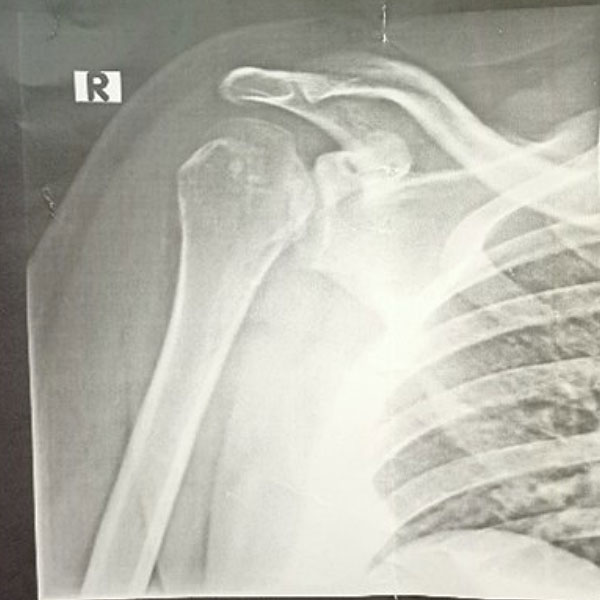

Initially, the patient had presented to an emergency room, where he had stated that his pain was the result of his friend having gently pulled his shoulder while joking around. Upon a subsequent X-ray (fig. 1) the patient had been diagnosed with a shoulder contusion.